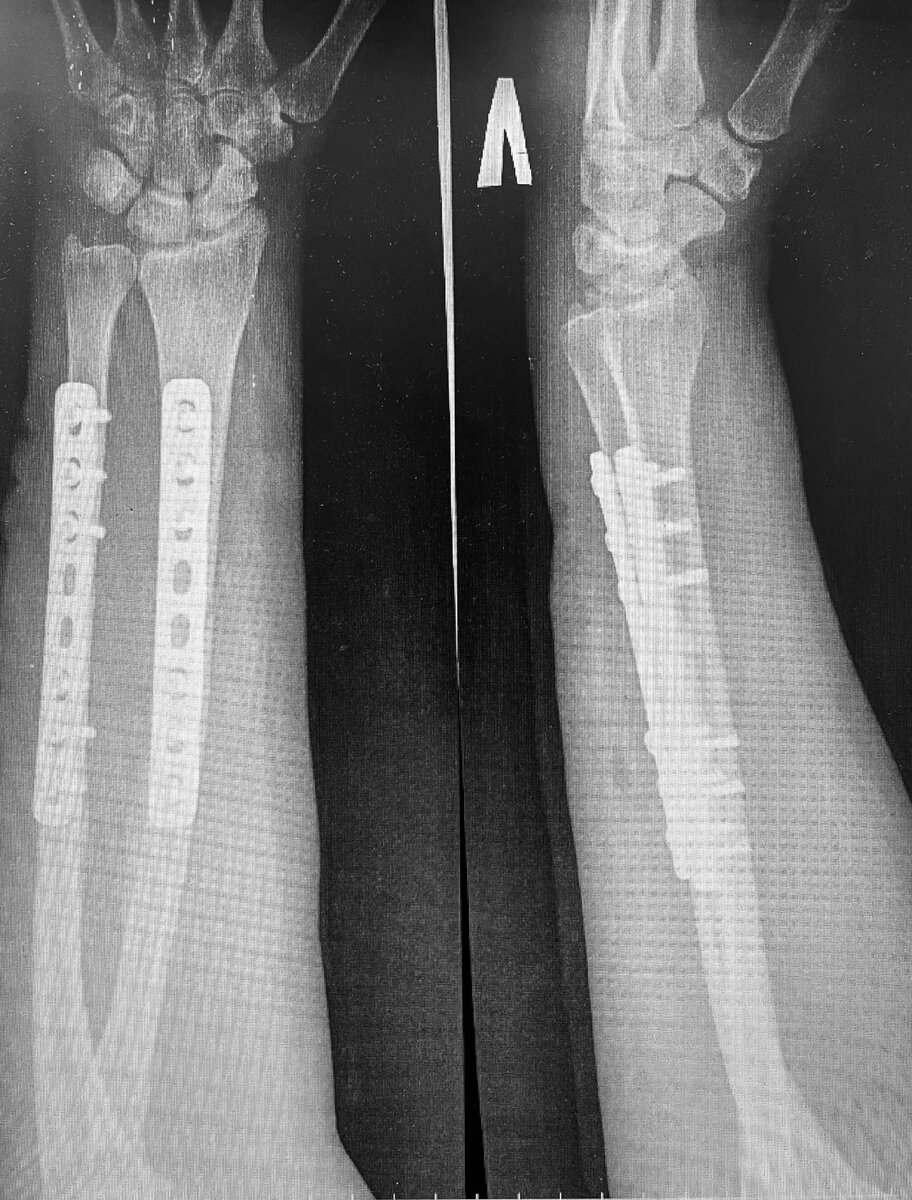

R-гр. левого предплечья в двух проекциях: перелом с/3 локтевой кости со смещением, перелом с/3 лучевой кости со смещением

На рентгенограмме состояние после МОС, стояние отломков удовлетворительное